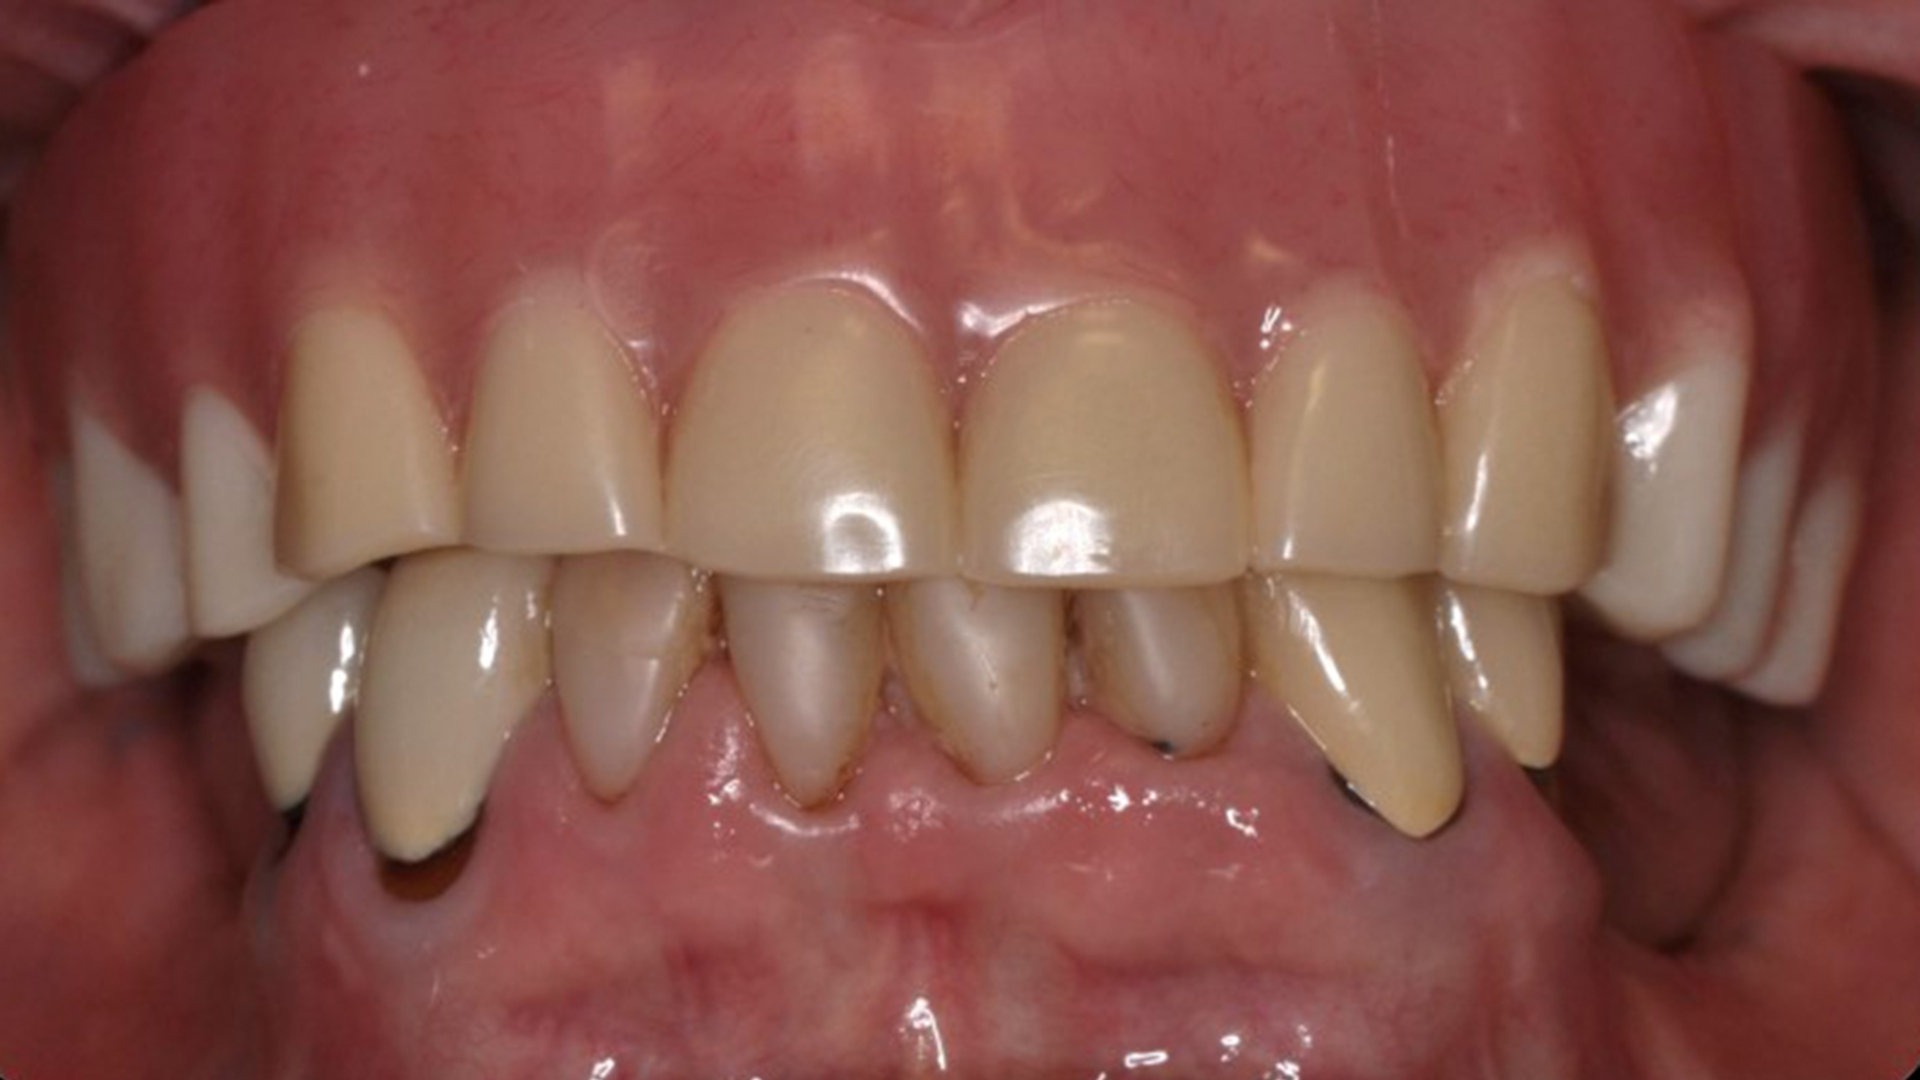

Fig. 19: Final implant-supported prosthesis.

The finished overdenture was tried in with the SynCone caps seated on the abutments, and passive fit was confirmed, as were the occlusion and aesthetics. Chairside resin was placed into the sites in the intaglio surface of the denture where the abutment spaces were present. The overdenture was then seated intra-orally, and the patient instructed to occlude. Upon setting of the resin, the overdenture was removed with the SynCone caps embedded within. Any resin flash around the SynCone caps was removed and the areas polished. The overdenture was reinserted intra-orally, and retention and occlusion were confirmed (Fig. 19). The patient was scheduled for a follow-up appointment the following week to check fit and function.